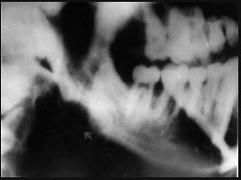

常引起边缘性骨髓炎的间隙感染是 ( )

A.颊间隙B.咬肌间隙C.颏下间隙D.颌下间隙E.眶下颊间隙

B